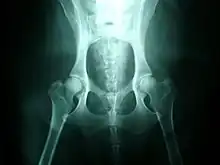

Normal hips, for comparison